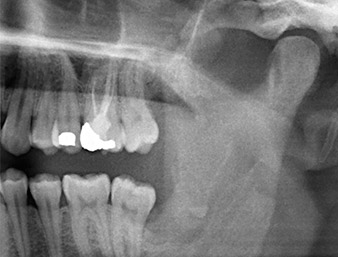

À l’OPG, le reste radiculaire dans la région de la dent 38 (LL8) apparaît déjà très proche du nerf alvéolaire inférieur. La racine s’est fracturée pendant l’ostéotomie mais n'a pas été extraite par le prestataire de soins primaires en raison de douleurs peropératoires. Pour minimiser le traumatisme causé aux tissus, la nouvelle ostéotomie devait être réalisée par piézochirurgie. Le patient ne présente pas d’antécédents médicaux particuliers et est non-fumeur.

On voit sur l’image 3D (tomographie volumétrique numérique) que le reste radiculaire est en position disto-caudale au niveau de la transition de la partie horizontale vers la partie ascendante de la mandibule (Fig. 2).

Compte tenu de ses antécédents médicaux, notre patient (26 ans, non-fumeur) présentait de très bonnes chances

de réussite. L’OPG ayant révélé que le reste radiculaire était très proche du nerf alvéolaire inférieur, une tomographie volumétrique numérique a été effectuée en plus (6).